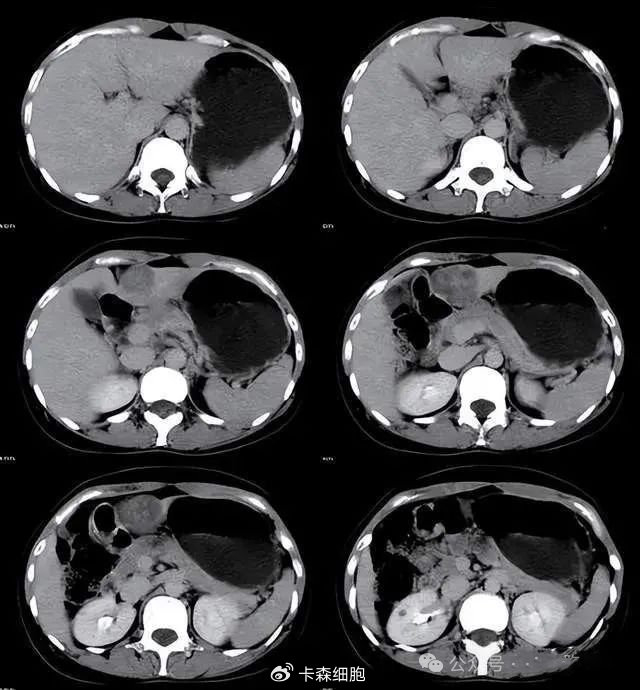

晚期弥漫性肝癌,经治疗后肿瘤缩小,生活质量显著提高

肝愿同行丨免疫联合治疗2周期后pr,伴门静脉癌栓的弥漫性肝癌患者迎新

真实案例分享:弥漫性肝癌合并门静脉癌栓,还有方法治疗吗?